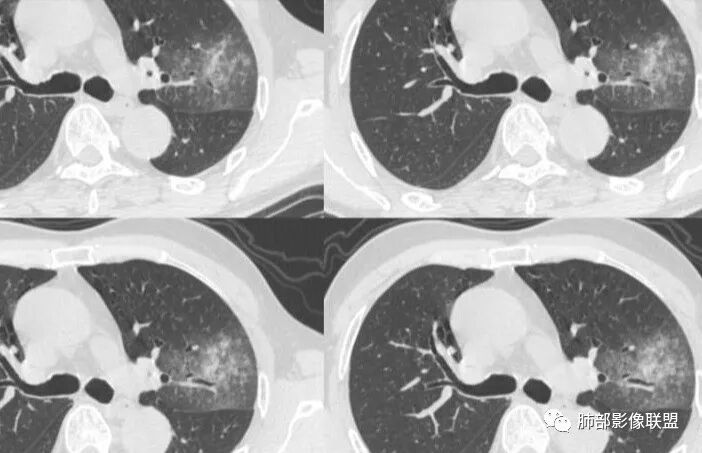

这三个月后的

大雄:

我只是要告诉大家,不是二元,就是肿瘤,没有什么感染,磨玻璃都没消失。

低分化腺癌坏死常见,转移的淋巴结坏死也常见,这个奇怪的就是淋巴结没有转移,如果有淋巴结肿大,应该会更容易想到低分化腺癌。

@小赵 这个不一定是粘液,很可能还是周围癌性浸润。看术前复查,原磨玻璃区呈明显小叶间隔增厚改变了。说明还是癌性淋巴浸润。

@温附一影像科,傅钢泽 应该是STA(气腔播散)加癌性淋巴管炎。

反思,恶性膨隆,远端空洞,强化坏死不均,里面血管似乎也是增粗,边界不清,似乎有侵犯。坏死还是边界不清。